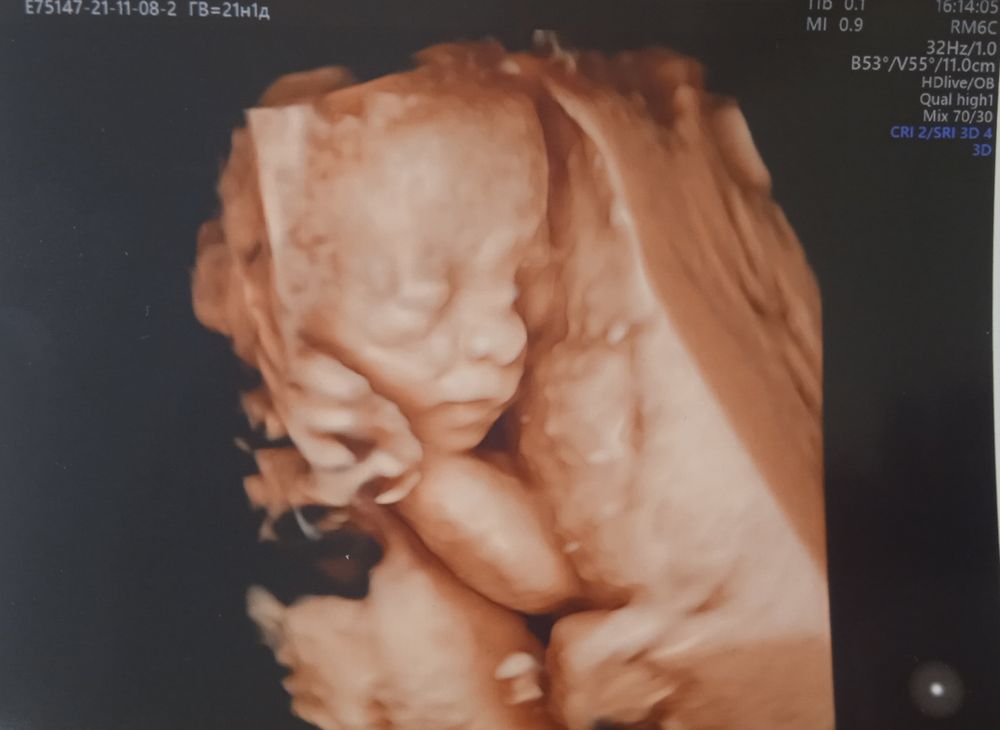

Лучше всего личико видно, когда ещё много околоплодных вод, 21-23 недели должно быть ещё норм. Я не помню, на каком сроке прошлый раз была, но вот в 31 неделю уже толком не посмотришь, т.к. тесновато, у него то ручки перед лицом, то пуповина, то в матку упёрся мордашкой

Почти 31 неделька и 21 неделька